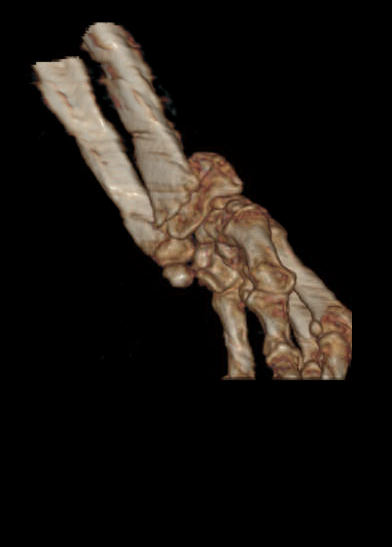

术前肱骨头CT

1、右肱骨近端骨折(Neer 4部分)